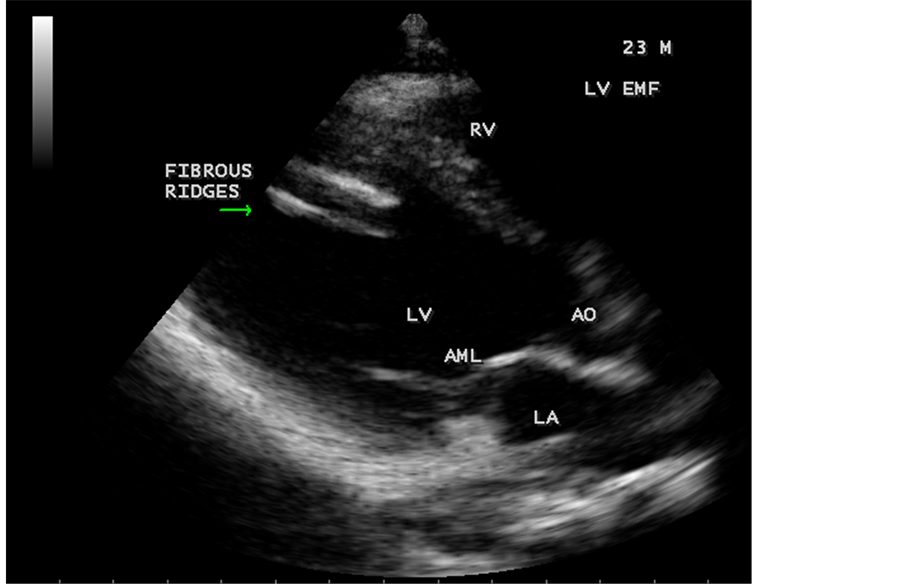

Figure 45. Endomyocardial fibrosis showing thickening of LV tendons seen as fibrous ridges as an initial manifestation of LV EMF in a 23-year-old male.

Figure 46. Showing RV EMF with fibrosed and thickenned moderator band in a 16-year-old female in cardiac type TAPVC (total anomalous pulmonary venous connection) with ASD (atrial septal defect).

When the endocardium is replaced by collagenous fibrosis (consists of collagen deposition and fibroblast proliferation), the final fibrotic stage is reached after several years of disease activity. Fibrotic obliteration of the apices of the affected ventricles is the hallmark of the disorder and fibrosis involving the papillary muscles and chordae tendineae leading to atrioventricular valve distortion and regurgitation. In the left ventricle, the fibrosis extends from the apex to the posterior mitral leaflet, usually sparing the anterior mitral leaflet and outflow tract and cause PML (posterior mitral leaflet) distortion and regurgitation. Like the peculiar geographical distribution, the fibrotic endomyocardial involvement stops short of the ventricular outflow tract like a ridge [17] as shown in Figure 15, Figure 29, Figure 31, Figure 35 and Figure 45. The fibrotic tissue often creates a nidus for thrombus formation, which can be extensive. Atrial thrombi also occur and the right atrium may be aneurysmally dilated. Aneurysmal right atrium with spontaneous echo contrast was detected in a 32-year-old male as shown in Figure 36 ( [18] , Figure 3]). In addition, there are fibrosis and granular septation extending into the underlying myocardial tissue and myocyte hypertrophy is common [19] . Fibrotic process causes tethering of leaflets into ventricular walls and may mimic Ebstein’s malformation as shown in Figure 39 and Figure 66 [20] [21] . Fibrosis increases the stiffness of the heart, resulting restrictive physiology, AV (atrioventricular) valve regurgitation which has been linked to atrial arrhythmias such as atrial fibrillation as shown in Figure 19 and Figure 20 in a 62-year-old female. Atrial fibrillation has been reported in more than 30% of patients with EMF. Fibrosis impairs activation patterns of the conduction system and may provide substrate for wave breaks and reentry [22] . Fibrosis reduces conduction velocity and cause conduction abnormalities like junctional rhythms, heart blocks as shown in Figure 21 and Figure 22 in a 75-year- old female and atrioventricular conduction delay [23] .

Today echocardiography is used as the screening tool at the community level as the diagnosis of EMF could be confirmed at the bedside. Echocardiography accurately assesses the pathological abnormalities of chronic disease and it is the gold standard technique for the diagnosis of EMF [36] . It reveals dense endomyocardial echocardiograms along different parts of the mural and valvular endocardium and AV valve dysfunction [37] as shown in Figure 3 to Figure 7, Figure 10 to Figure 15, Figure 17, Figure 18, Figure 20 to Figure 75 and Figure 78 to Figure 84. The typical feature of EMF is the obliteration of trabecular portion of the ventricle and in advanced cases, there is shrinkage of the cavities creating an apical notch, regurgitation, slow flow with spontaneous echo contrast as in Figure 36 and considerable pericardial effusion. Similar to apical notch of right ventricle, a right atrial notch is well seen as contraction (or retraction) of tricuspid annulus as in Figure 41 and right atrial notch as in Figure 42 and Figure 43, indicating the retraction of right atrial cavity as a peculiar feature of right ventricular EMF. Biventricular enlargement as shown in Figure 41 and biatrial